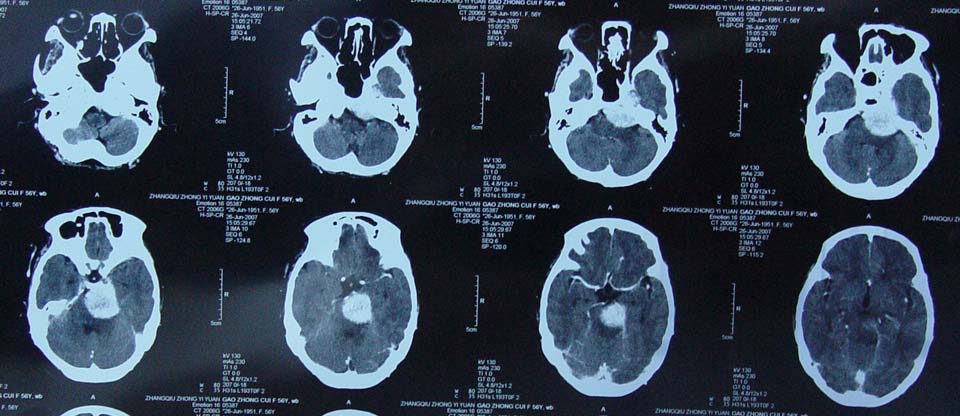

女性,56岁,查体所见,请会诊

平扫为较高密度,增强后病灶明显强化,边界清楚水肿不明显.考虑脑膜瘤.

左岩骨尖区脑膜瘤

从病变位置和强化表现看倾向脑膜瘤,但其跨越中后颅窝,也要结合临床,不能忽略三叉神经瘤,不过后者囊变较多。此病例的不足是无骨窗对照,脑膜瘤比较容易出现临近骨骼的异常。

左岩骨尖区占位病变,平扫呈高密度,病变跨中后颅窝生长,岩骨可见骨质吸收,周围未见明显水肿,增强扫描病灶明显强化。考虑左岩骨尖区脑膜瘤。

此片最大的缺憾是没骨窗,钙化及颅骨的改变不好看